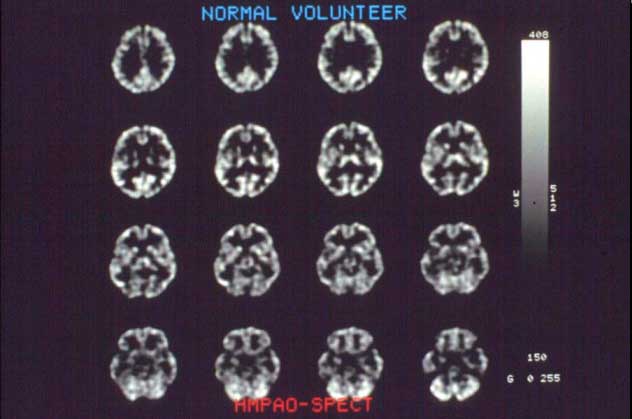

This slide shows a head SPECT image obtained at Kanazawa University. This image was named gImage of the Yearh by the Society of Nuclear Medicine in 1990. More than 100 3|detector SPECT systems have been delivered.